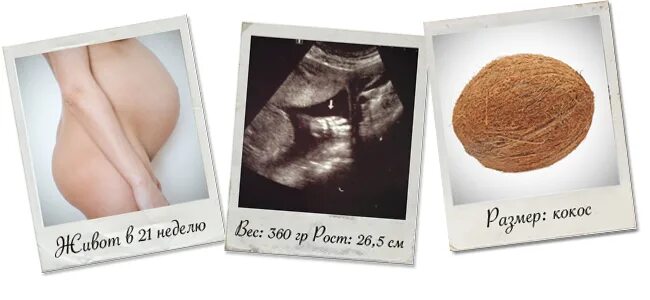

21 неделя и 4 дня